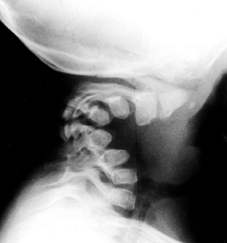

![]() |

|

Figure 180.7. Cervical kyphosis in a 2-year-old girl with diastrophic dysplasia.